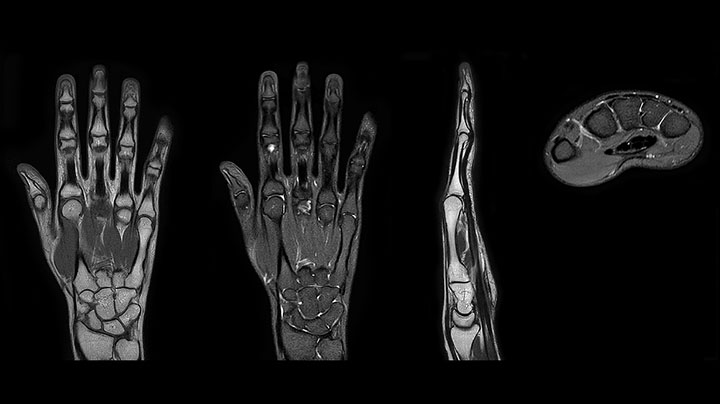

Prodiva imaging of the hand covers the fingertips and includes the full wrist as well. The dS MSK M coil is easy to use.

Scan time 2:55 min, FOV 160 mm, acq voxels 0.55 x 0.83 x 3.0 mm.

Scan time 4:19 min, FOV 160 mm, acq voxels 0.55 x 0.80 x 3.0 mm.

Scan time 2:50 min, FOV 160 mm, acq voxels 0.70 x 0.99 x 3.0 mm.

MRI of the finger with high SNR and good resolution in a 10 cm field of view on Prodiva 1.5T. The diagnosis in this 63-year-old patient is bone elasmanosis.